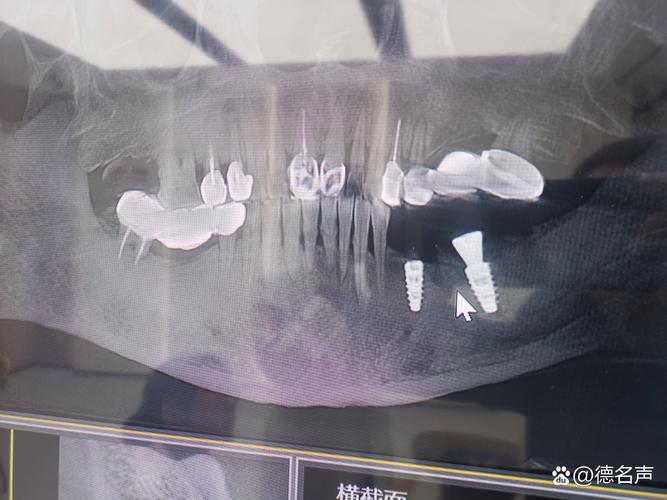

- 种植体穿入上颌窦: 种植体尖端可能穿透上颌窦底壁,进入窦腔,这会导致感染、疼痛、种植体松动、失败等严重后果。

- 初期稳定性差: 骨量不足会导致种植体植入后初期不够稳固,影响骨结合(种植体与骨头长牢)的成功率。

- 缺乏长期支持: 即使勉强植入,骨量不足也难以提供种植体长期承受咀嚼力所需的支撑。

上颌窦炎风险: 上颌窦本身有炎症或易感体质的患者,种植体靠近或穿入窦腔会大大增加感染和诱发/加重上颌窦炎的风险。